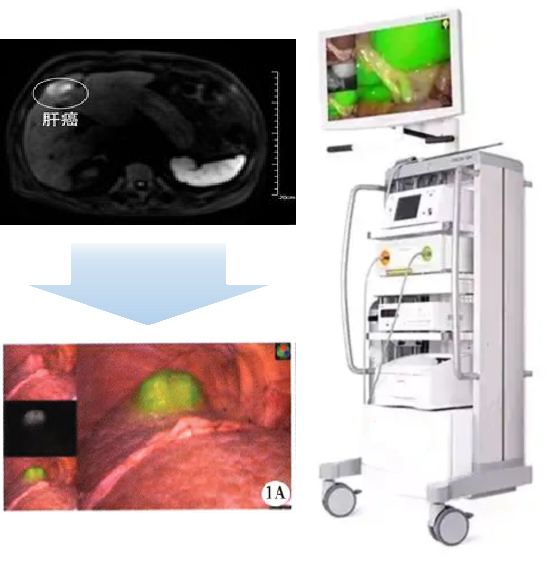

PL002是浙江普利藥業(yè)有限公司研發(fā)的熒光/磁共振雙模態(tài)造影劑,開發(fā)熒光/磁共振雙模態(tài)造影劑成為提高原發(fā)性肝癌手術(shù)效率的有效方案。雙模態(tài)造影劑的熒光成像能力可用于肝癌術(shù)中熒光導(dǎo)航,而磁共振增強能力可用于在術(shù)前判斷肝臟代謝能力,推測腫瘤及肝臟對造影劑的攝取情況,提高腫瘤診斷精度,降低術(shù)前規(guī)劃難度。

PL002相較于吲哚菁綠具有明顯優(yōu)勢。目前吲哚菁綠在臨床使用中存在給藥到手術(shù)時間不確定的問題,可能造成病灶與正常組織對比度不足,影響術(shù)中的病灶的判斷,PL002采用獨特的釓絡(luò)合物與熒光分子共價鍵結(jié)合的分子結(jié)構(gòu)設(shè)計,這種設(shè)計能夠讓醫(yī)生在術(shù)前通過磁共振成像確定造影劑在病灶中的聚集情況,進而針對患者個體情況來對手術(shù)時間進行規(guī)劃。同時,由于PL002體內(nèi)更為穩(wěn)定,在荷瘤小鼠模型中同等條件下熒光成像效果維持時間長于現(xiàn)有熒光造影劑,也保證了其在臨床應(yīng)用中具有更寬的手術(shù)窗口。

使用雙模態(tài)造影劑可以為手術(shù)醫(yī)生提供更加豐富的診斷信息,降低術(shù)中的決策壓力,避免過度切成,增加發(fā)現(xiàn)微小病灶的可能性,最終實現(xiàn)患者的全面獲益。此外,相較于傳統(tǒng)熒光造影劑,PL002的安全性更高、體內(nèi)更為穩(wěn)定,成像效果更佳,為其臨床使用提供了有效的支持。